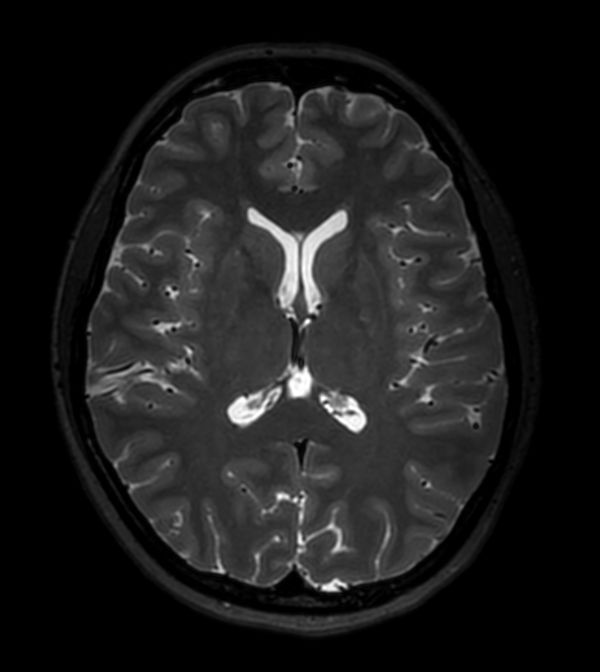

Axial SWIp (Modulus)

-

Axial SWIp (minIP)

Axial SWIp (Phase)